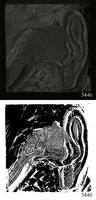

ASSU Illustration 3446

Block numbered in at least one place: 3446., Image of the inner and outer ear., Tape (inscribed “524”) on obverse.